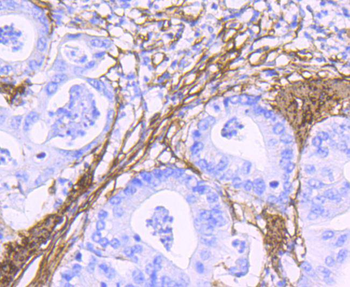

FC, ICC, IF, IHC-Fr, IHC-P, WB

Human

Mouse

Rabbit

Recombinant

Unconjugated

50 μl, 100 μl - MARK3 Recombinant Rabbit Monoclonal Antibody [orb704310]Featured